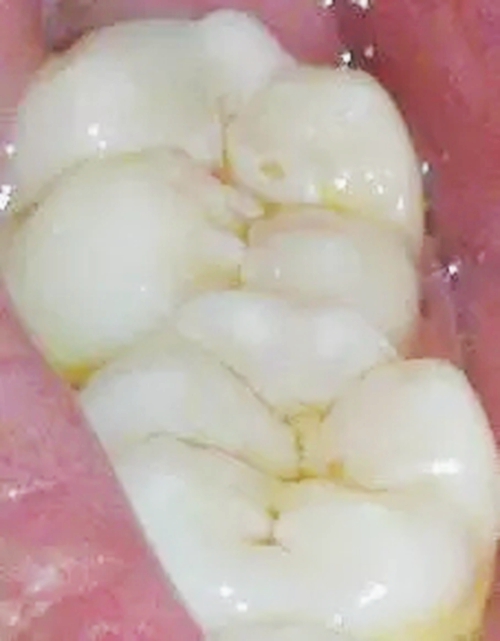

2,中齲

2.webp.jpg

齲壞已達(dá)牙本質(zhì)淺層,臨床檢查有明顯齲洞,可有探痛,對(duì)外界刺激(如冷、熱、甜、酸和食物嵌入等)可出現(xiàn)疼痛反應(yīng),當(dāng)刺激源去除后疼痛立即消失,無(wú)自發(fā)性痛。